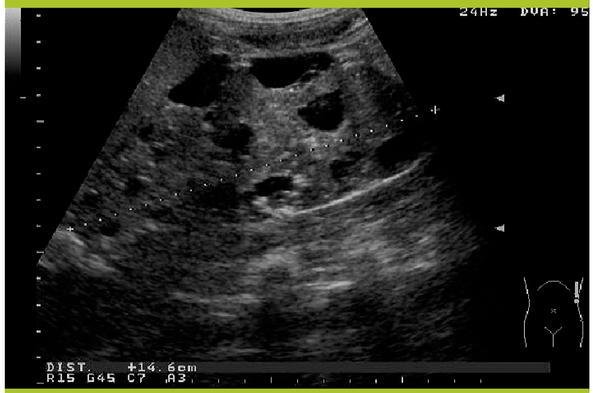

Masses Abdominopelviennes Chez Lenfant Introduction Diagnostic Positif Plan